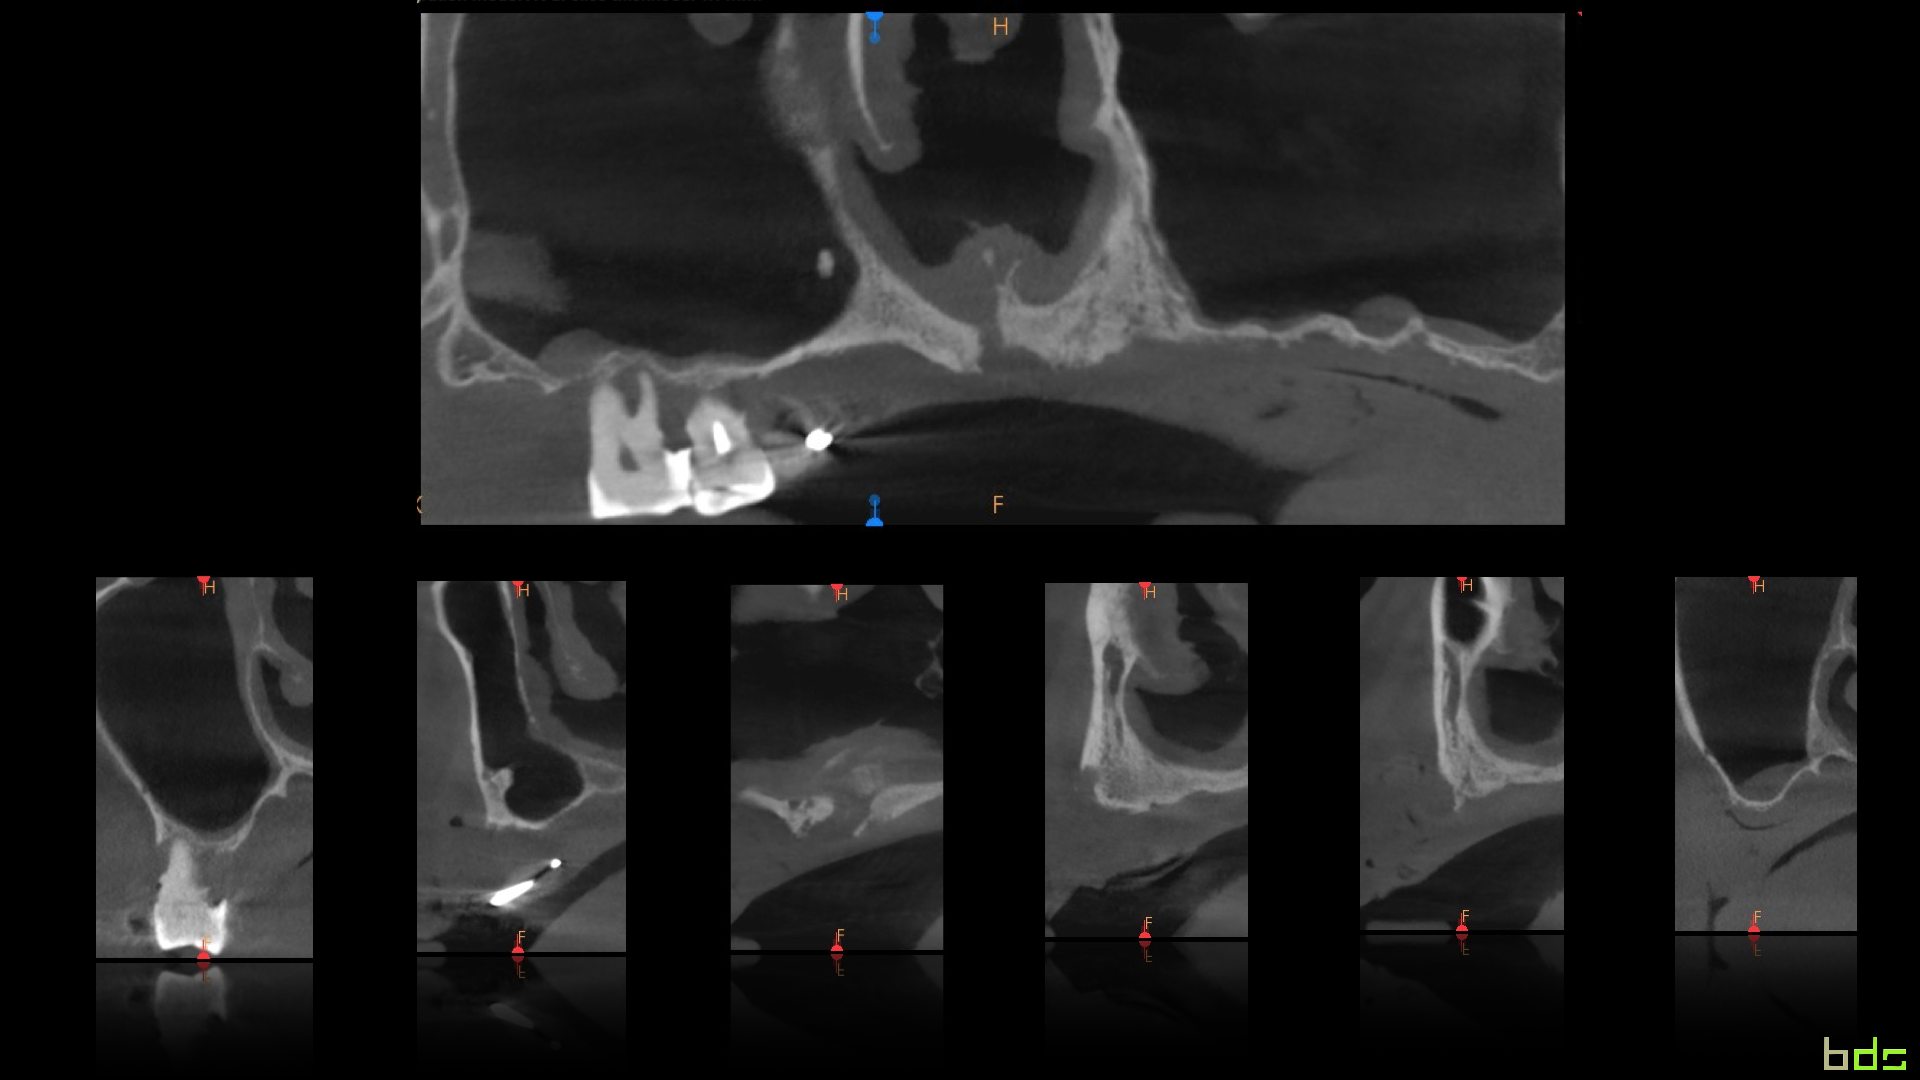

Pterygoid implants are an old therapeutic option for the

treatment of atrophic posterior maxilla that is often overlooked in today’s

treatment options. This lecture addresses the perceived anatomical risk that is

often associated with this procedure and tries to elucidate the controversies

on the subject. It will expose the scientific documentation of the procedure

and will present the modern approach in using the pterygoid implant for the

rehabilitation of totally and partially edentulous patients. The place of

guided surgery in performing this procedure is also discussed.